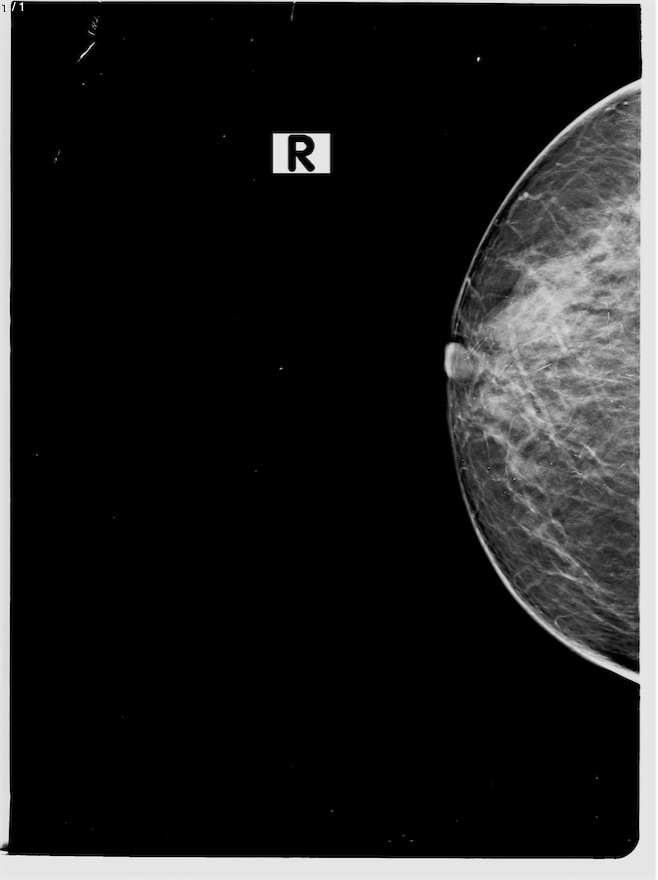

Amandina Solis Lopez - Unnamed